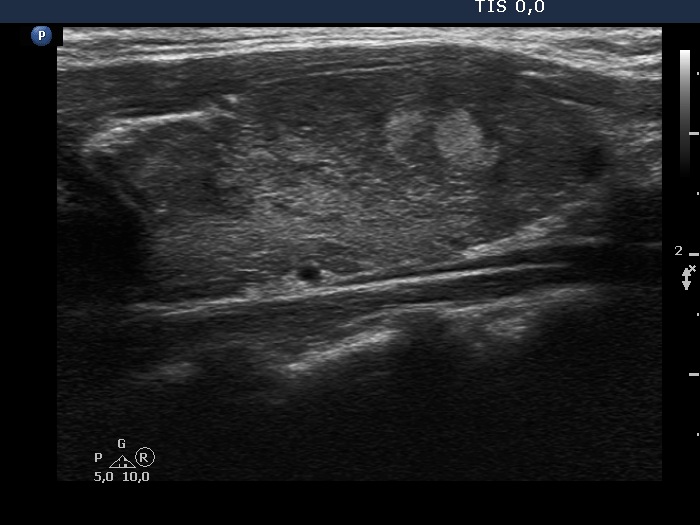

Left lobe, longitudinal scan

This is the usual course of Graves' disease regarding the change in echo pattern - before, during and after the activity of the autoimmune process. The only exception is the change in the size of the thyroid. In most cases, the thyroid increases during the activity of the disease, then returns to normal. However, in this patient the age counts: at the first examination, the patient was only 15-year-old.

- There are two situations in Graves 'disease where circulation is increased. At the stage of disease activity and when hypothyroidism is observed with medication. In the former case, the blood flow is almost always increased, in the latter it can be decreased and increased.